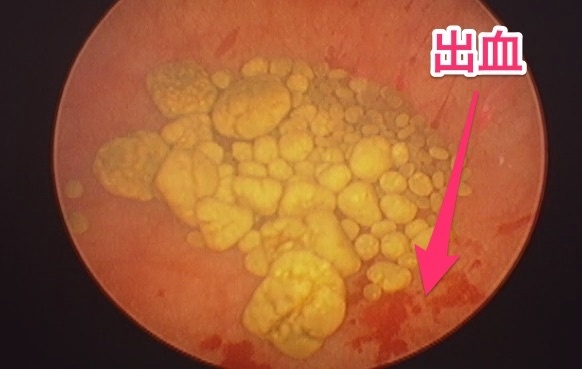

奥に黄色いものがたくさんあるのが分かりますか?これが膀胱結石です。いっぱいありますね。いつも思うんですが、結構キレイで、まるで金の塊のように見えますね。

そして、尿を洗浄すると、透明度が増してよく見えてきます、結石の周辺の粘膜から、結石の刺激で出血しているのが見えますね。結石による慢性的な刺激は粘膜の肥厚や出血を起こすのがよくわかります。